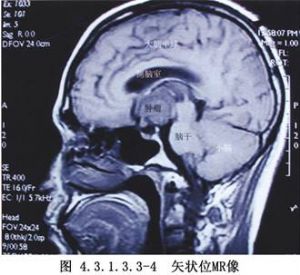

近年來,由於顯微神經外科技術的提高,經翼點入路在顱內腫瘤及動脈瘤手術中的應用日益廣泛。對顱咽管瘤切除術而言,由於這種入路稍加改變就能充分地顯露視交叉前後、視神經-頸內動脈間隙及頸內動脈外側間隙,甚至小腦幕邊緣及頸內動脈分叉部附近的結構,故其適應證較寬。有人(Yasargil,1990)將其用作切除各種顱咽管瘤的主要手術入路(圖4.3.1.3.3-1~4.3.1.3.3-4)。